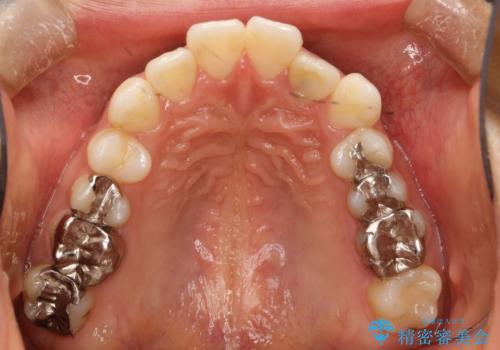

インビザラインで目立たない矯正 ガタガタの歯並びをきれいな歯並びへ

- 全体的なガタガタが気になるとのことで来院されました。

歯と歯のあいだをわずかに削りスペースを作り、ガタガタを改善する計画としました。